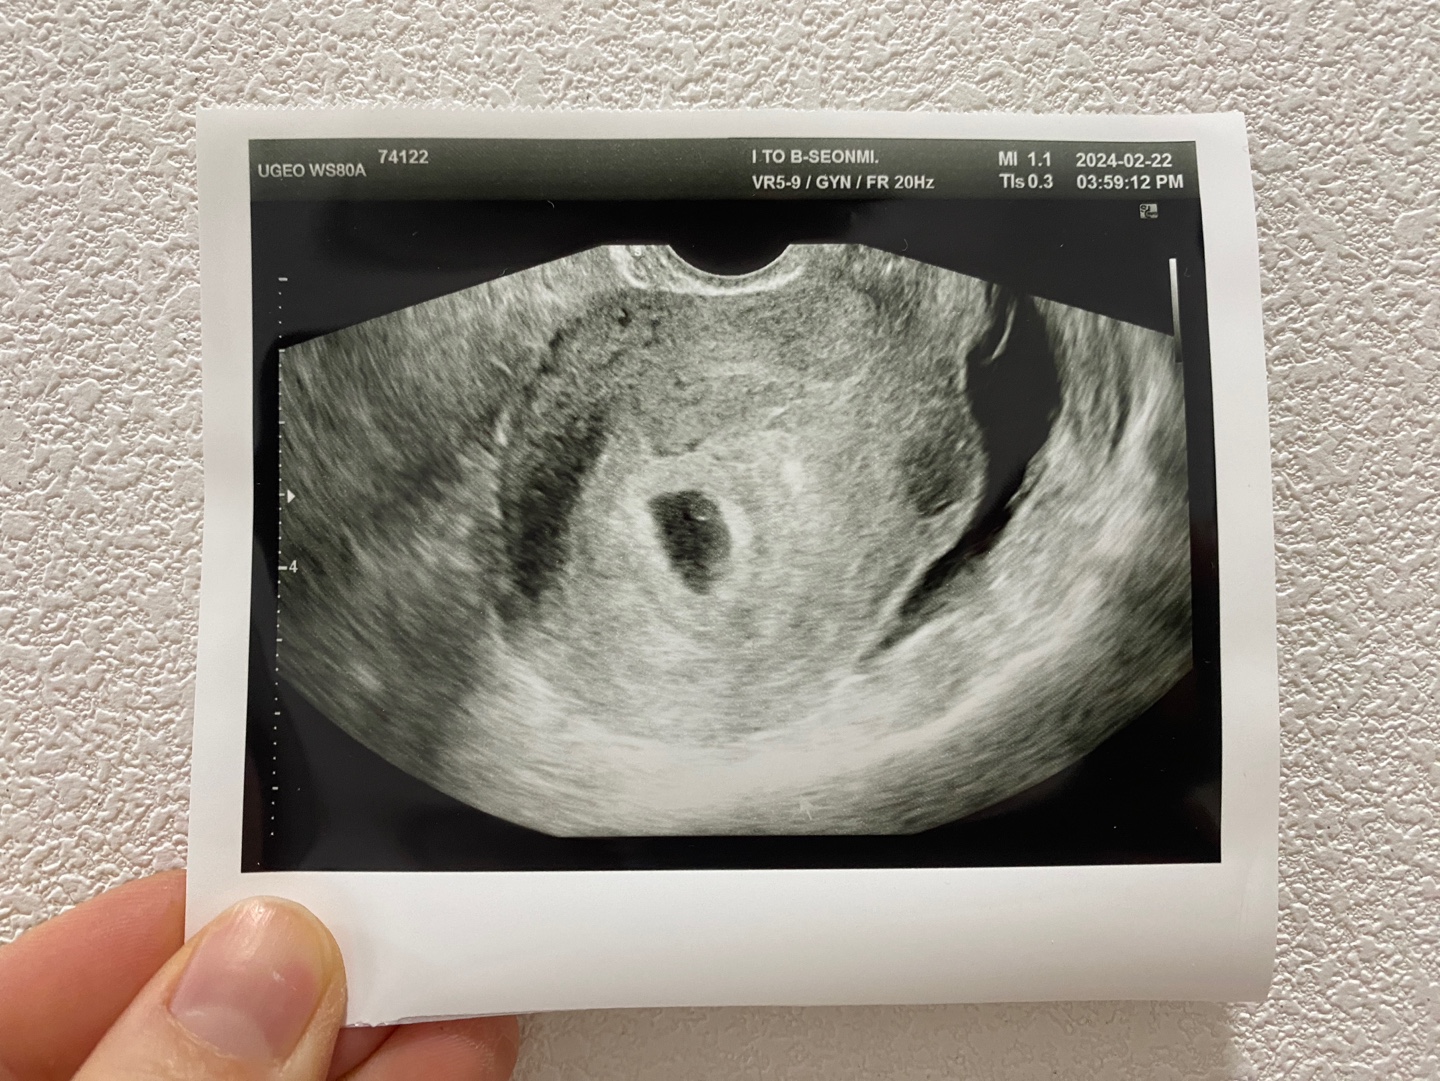

이 때 병원에 가시면, 초음파를 통해 아기집을 확인하실 수 있습니다.

아기와 난황은 아직 확인하실 수 없을 수도 있어요.

임신 6~7주차는 아기 심장소리를 들을 수 있는 시기입니다.

임신 6주차에 병원을 방문하셔서 아기집과 난황, 그리고 아기의 심장소리까지 들어보세요.

저는 6주차를 못 기다리고 5주차에 병원에 가서, 선생님이 2주 뒤에 오라고 하시더라구요~